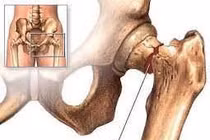

SuperPath là một trong kỹ thuật thay khớp háng tiên tiến nhất hiện nay. Phương pháp này được chỉ định phẫu thuật rộng rãi các bệnh lý khớp háng khác nhau như: hoại tử chỏm xương đùi, thoái hóa khớp háng, gãy cổ xương đùi...

Gãy cổ xương đùi rất thường gặp ở người lớn tuổi, nhiều trường hợp chỉ cần ngã nhẹ, đập hông xuống đất hoặc mặt cứng cũng có thể dẫn đến gãy. Vì vậy, người cao tuổi cần thận trọng phòng tránh té ngã trong mọi không gian, hoàn cảnh sống.